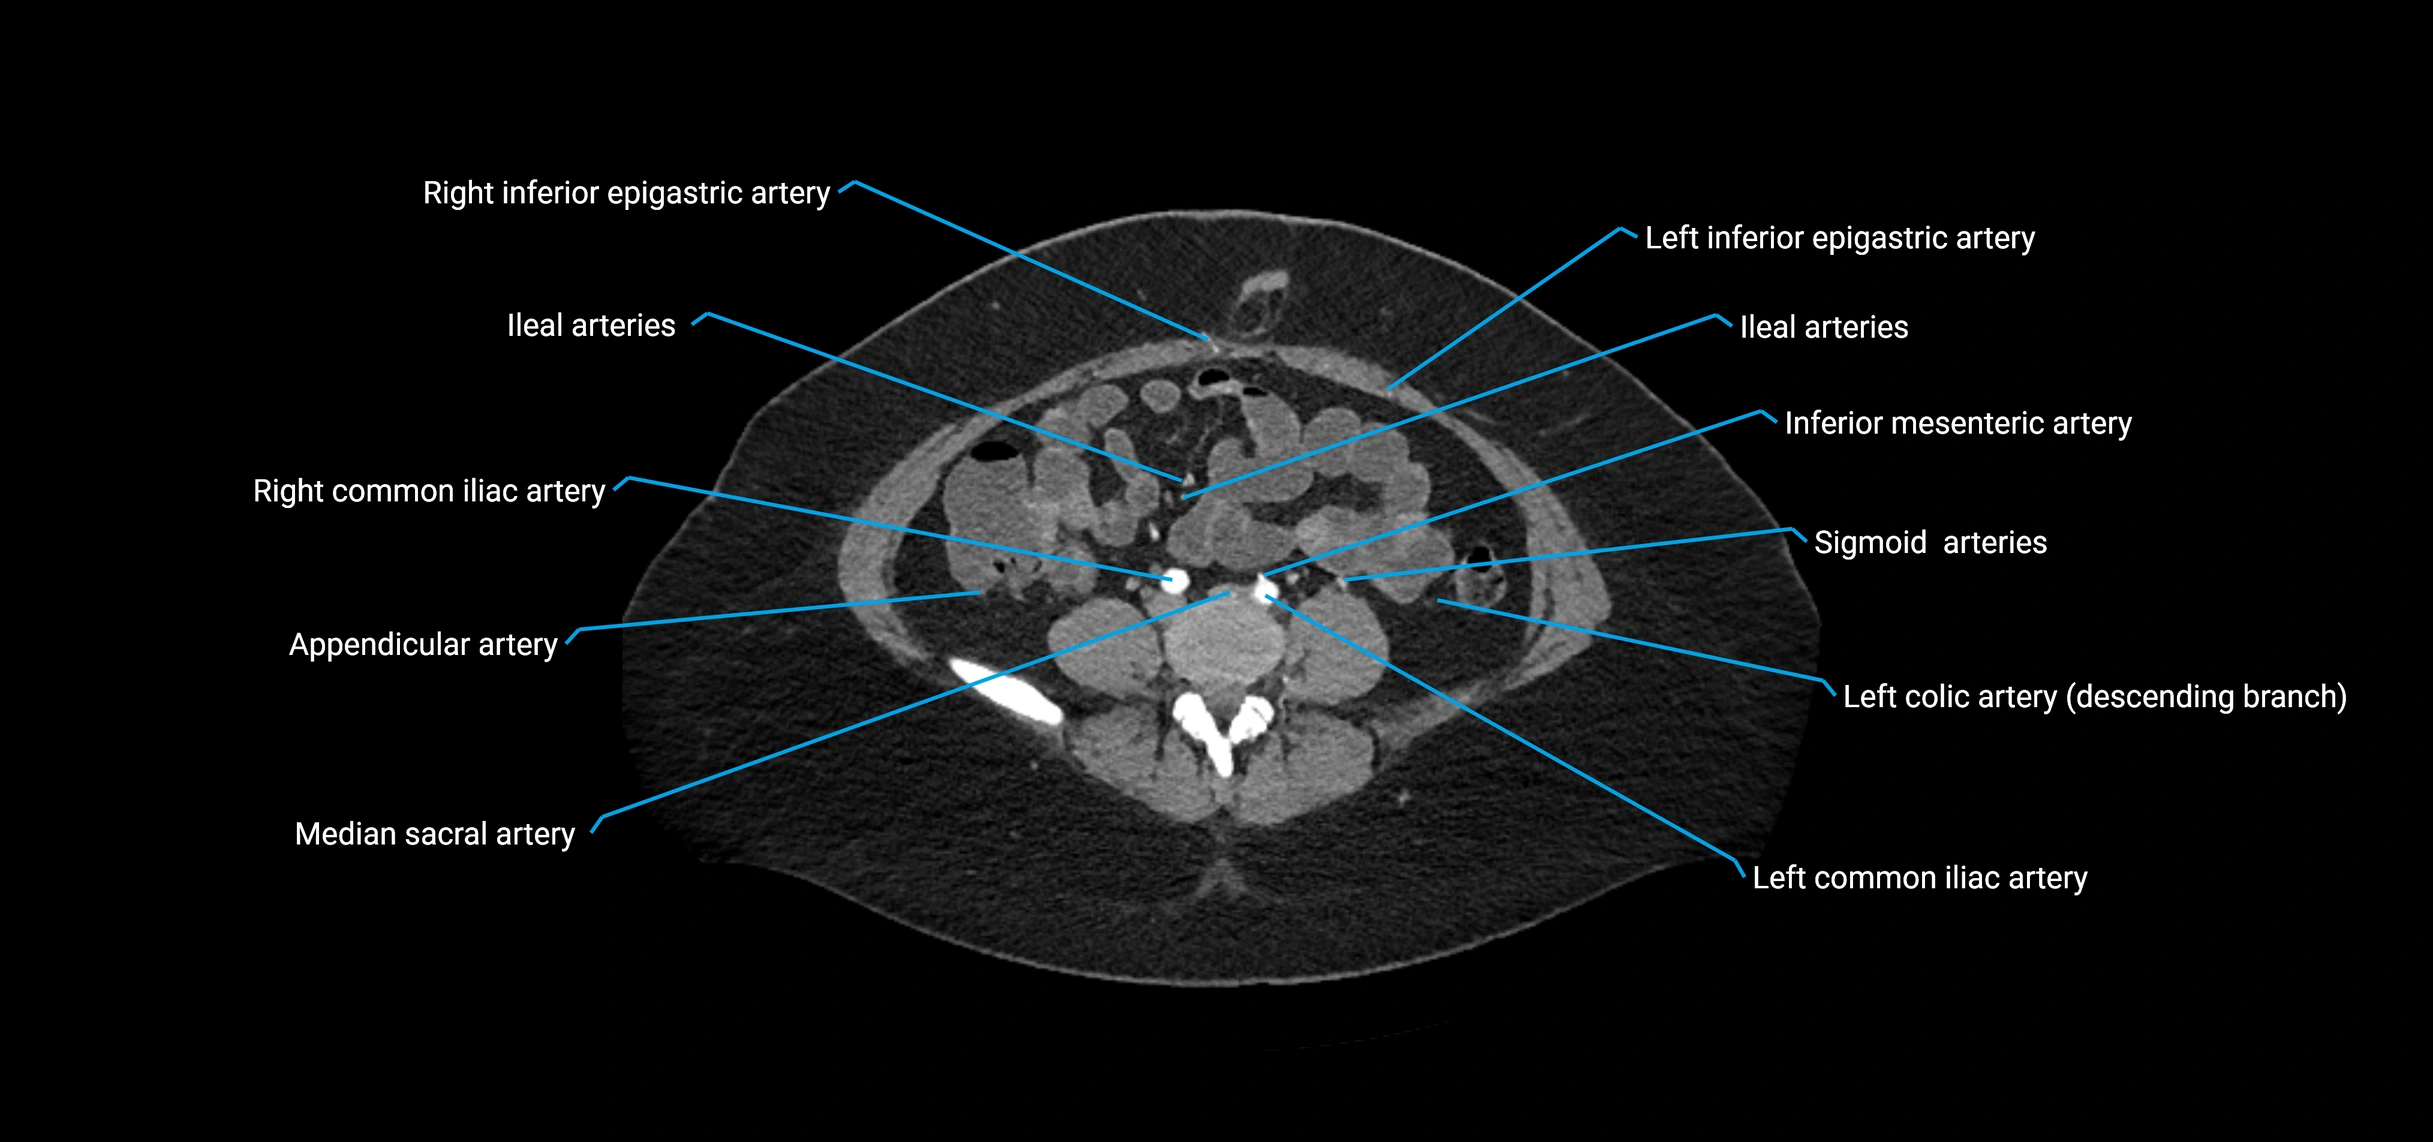

CT images

image

Contrast-enhanced CT (CTA):

• Gold standard for abdominal aortic imaging

• Provides excellent detail of lumen, wall, aneurysm, thrombus, and branch vessels

• Multiplanar and 3D reconstructions help in aneurysm measurement, stent graft planning, and dissection evaluation